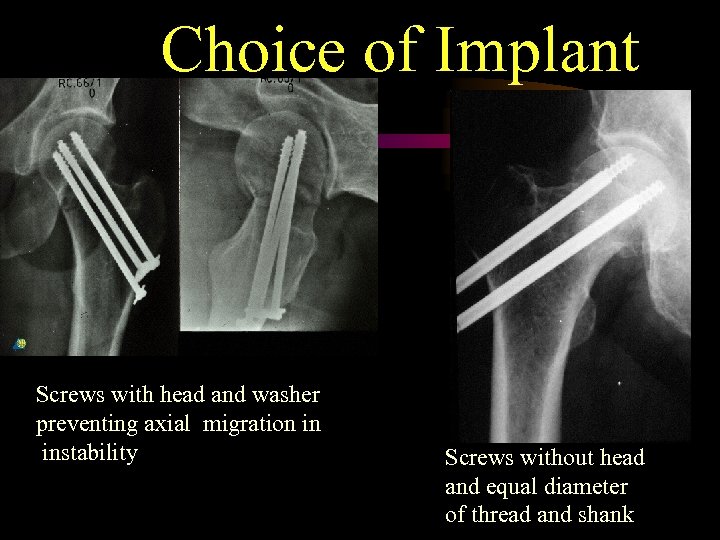

Choice of Implant Screws with head and washer preventing axial migration in instability Screws without head and equal diameter of thread and shank

Choice of Implant Screws with head and washer preventing axial migration in instability Screws without head and equal diameter of thread and shank